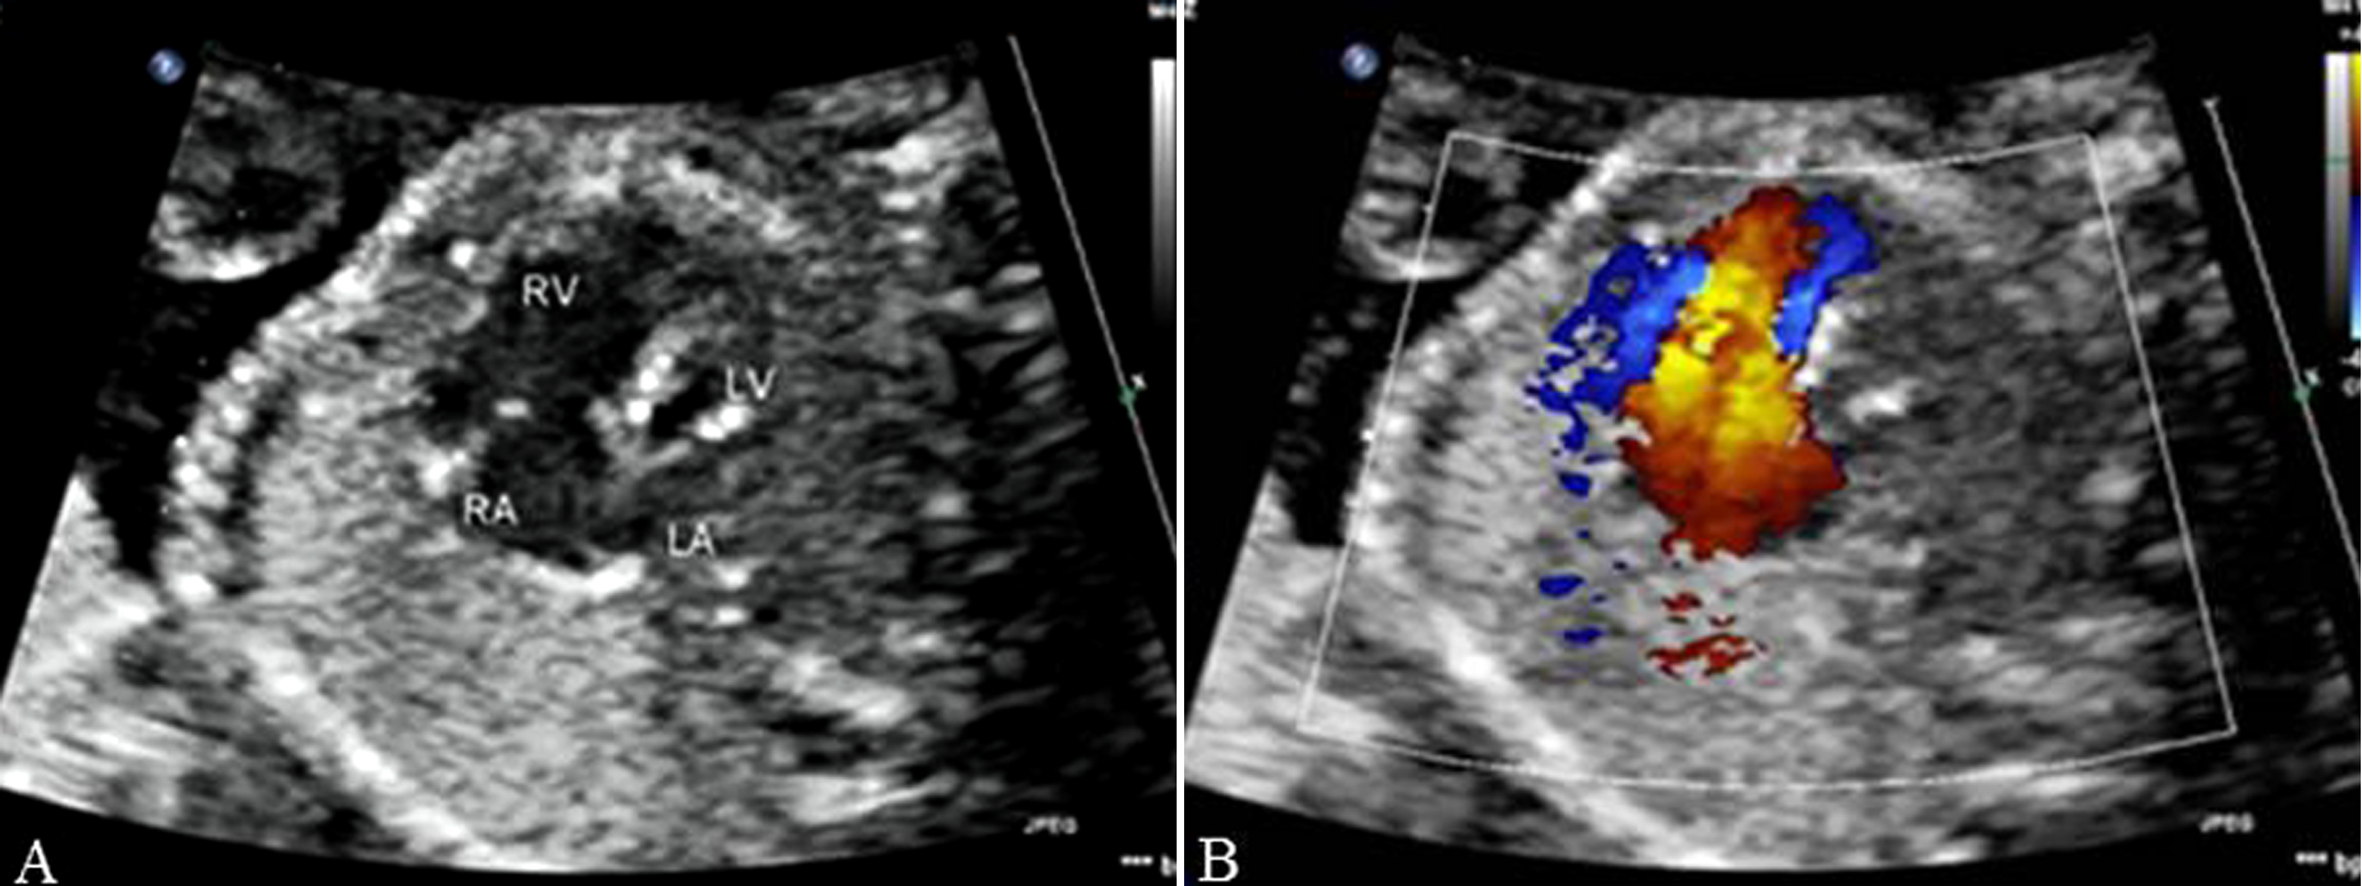

2. 超声诊断要点 二维超声显示左、右心室不对称,左心室明显小于右心室,心轴明显左偏;如伴有二尖瓣闭锁,则左心室内可不显示彩色多普勒血流信号(图1)。彩色多普勒超声检查三血管气管切面主动脉弓与动脉导管血流方向不一致,主动脉弓血流不是流向降主动脉,而是由动脉导管反流而来(图2)。

图1 胎儿左心发育不良综合征:LV<RV,心轴明显左偏